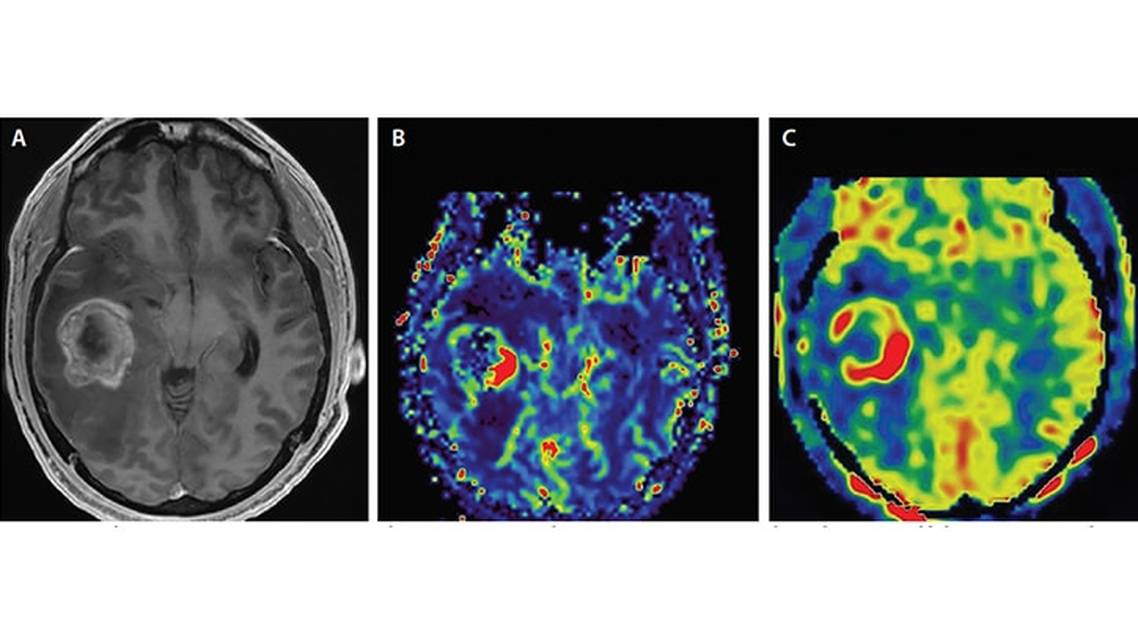

There is a positive correlation between rCBV and glioma grade as well as biologic activity; rCBV is usually elevated in grade 3 and higher in grade 4 (Figure 1).6,9 Adjuvant radiation therapy or chemotherapy is usually done only after resection of high-grade gliomas, DSC-MRI is an important approach to treatment decision making in addition to a histopathologic assessment of gliomas. The DSC-MRI perfusion images can also guide biopsy targeting the portion of a heterogeneous tumor with highest rCBV, which reflects the highest-grade tumor regions. Such targeting may decrease the chances of undergrading gliomas.10,11

Clinical Uses. Measurement of CBF with ASL perfusion imaging is used for tumor diagnosis, grading, follow up, and treatment. Hypo- or hyperperfusion can be identified and enables a comparison between multiple measurements in a longitudinal manner. For detecting tumors (eg, gliomas, metastases, and meningioma), ASL can be as accurate as DSC-MRI (Figures 1 and 2).17,18 Pulsed arterial spin labeling (PASL) technique can differentiate hemangioblastomas from metastatic tumors and pilomyxoid astrocytomas from pilocytic astrocytomas.19,20 Because primary central nervous system lymphomas (PCNSLs) have decreased perfusion, these can also be distinguished from glioblastoma with ASL.21 High- and low-grade gliomas can be distinguished with perfusion quantification with continuous arterial spin labeling (CASL) and PASL,22 and perfusion in high-grade tumors can be measured before and after treatment to assess response to treatment and progression. For distinguishing radiotherapy-induced necrosis from high-grade glioma recurrence, ASL is reported to be more effective than DSC (sensitivity > 90 %).23